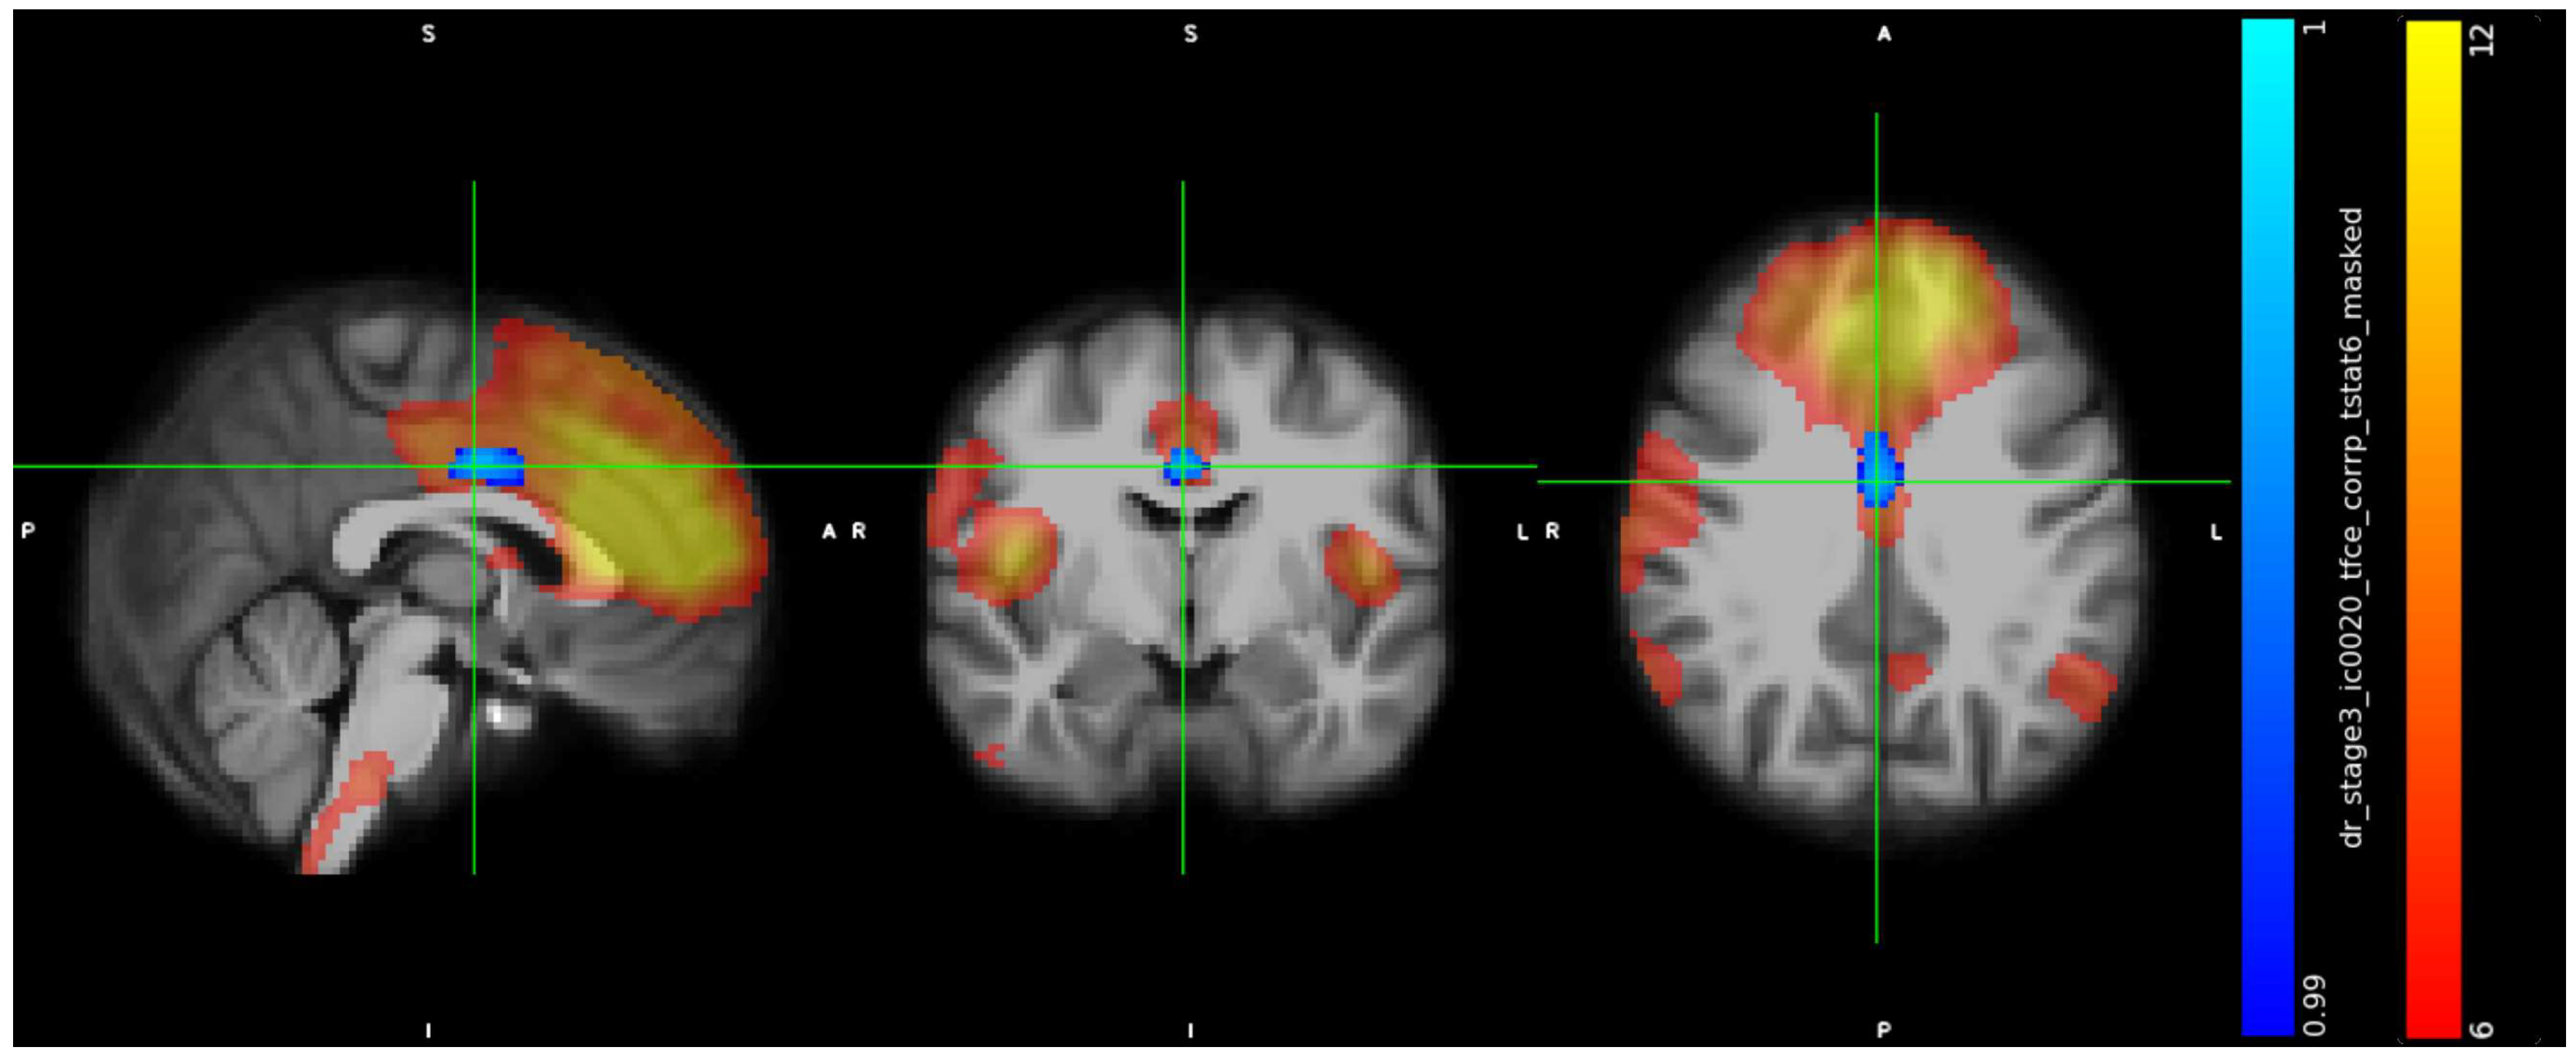

3.2. IC Analysis and Dual Regression